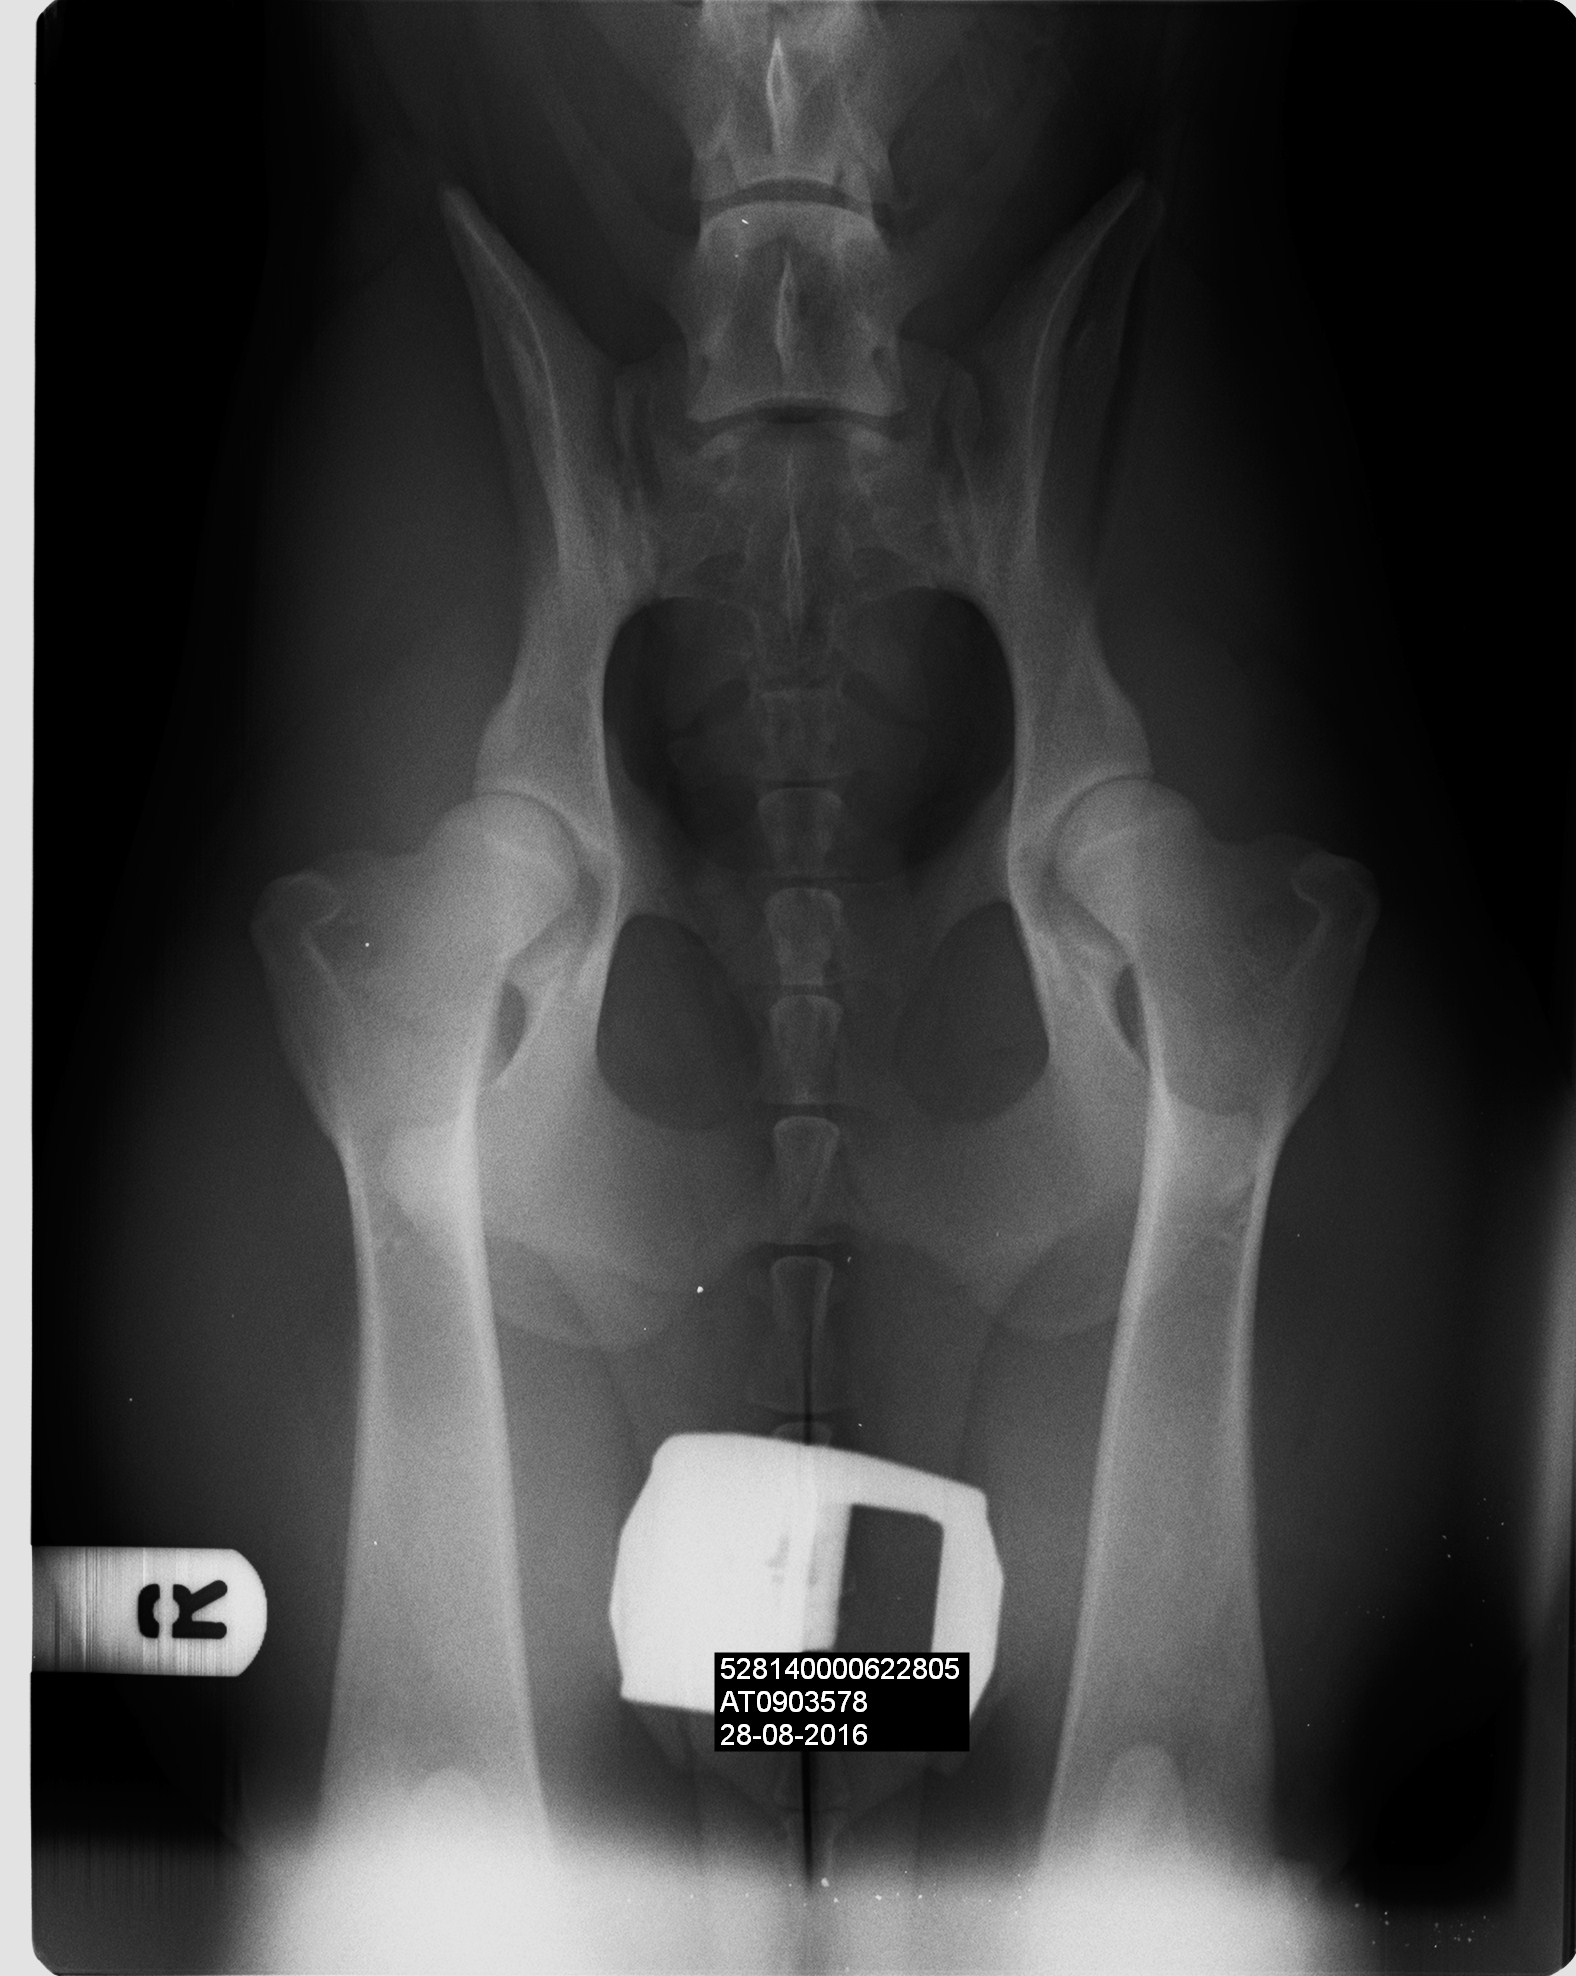

arrack-s-home-xia0000 Published October 14, 2016 at 1576 × 1976 in Xia’s health results are back! Next →